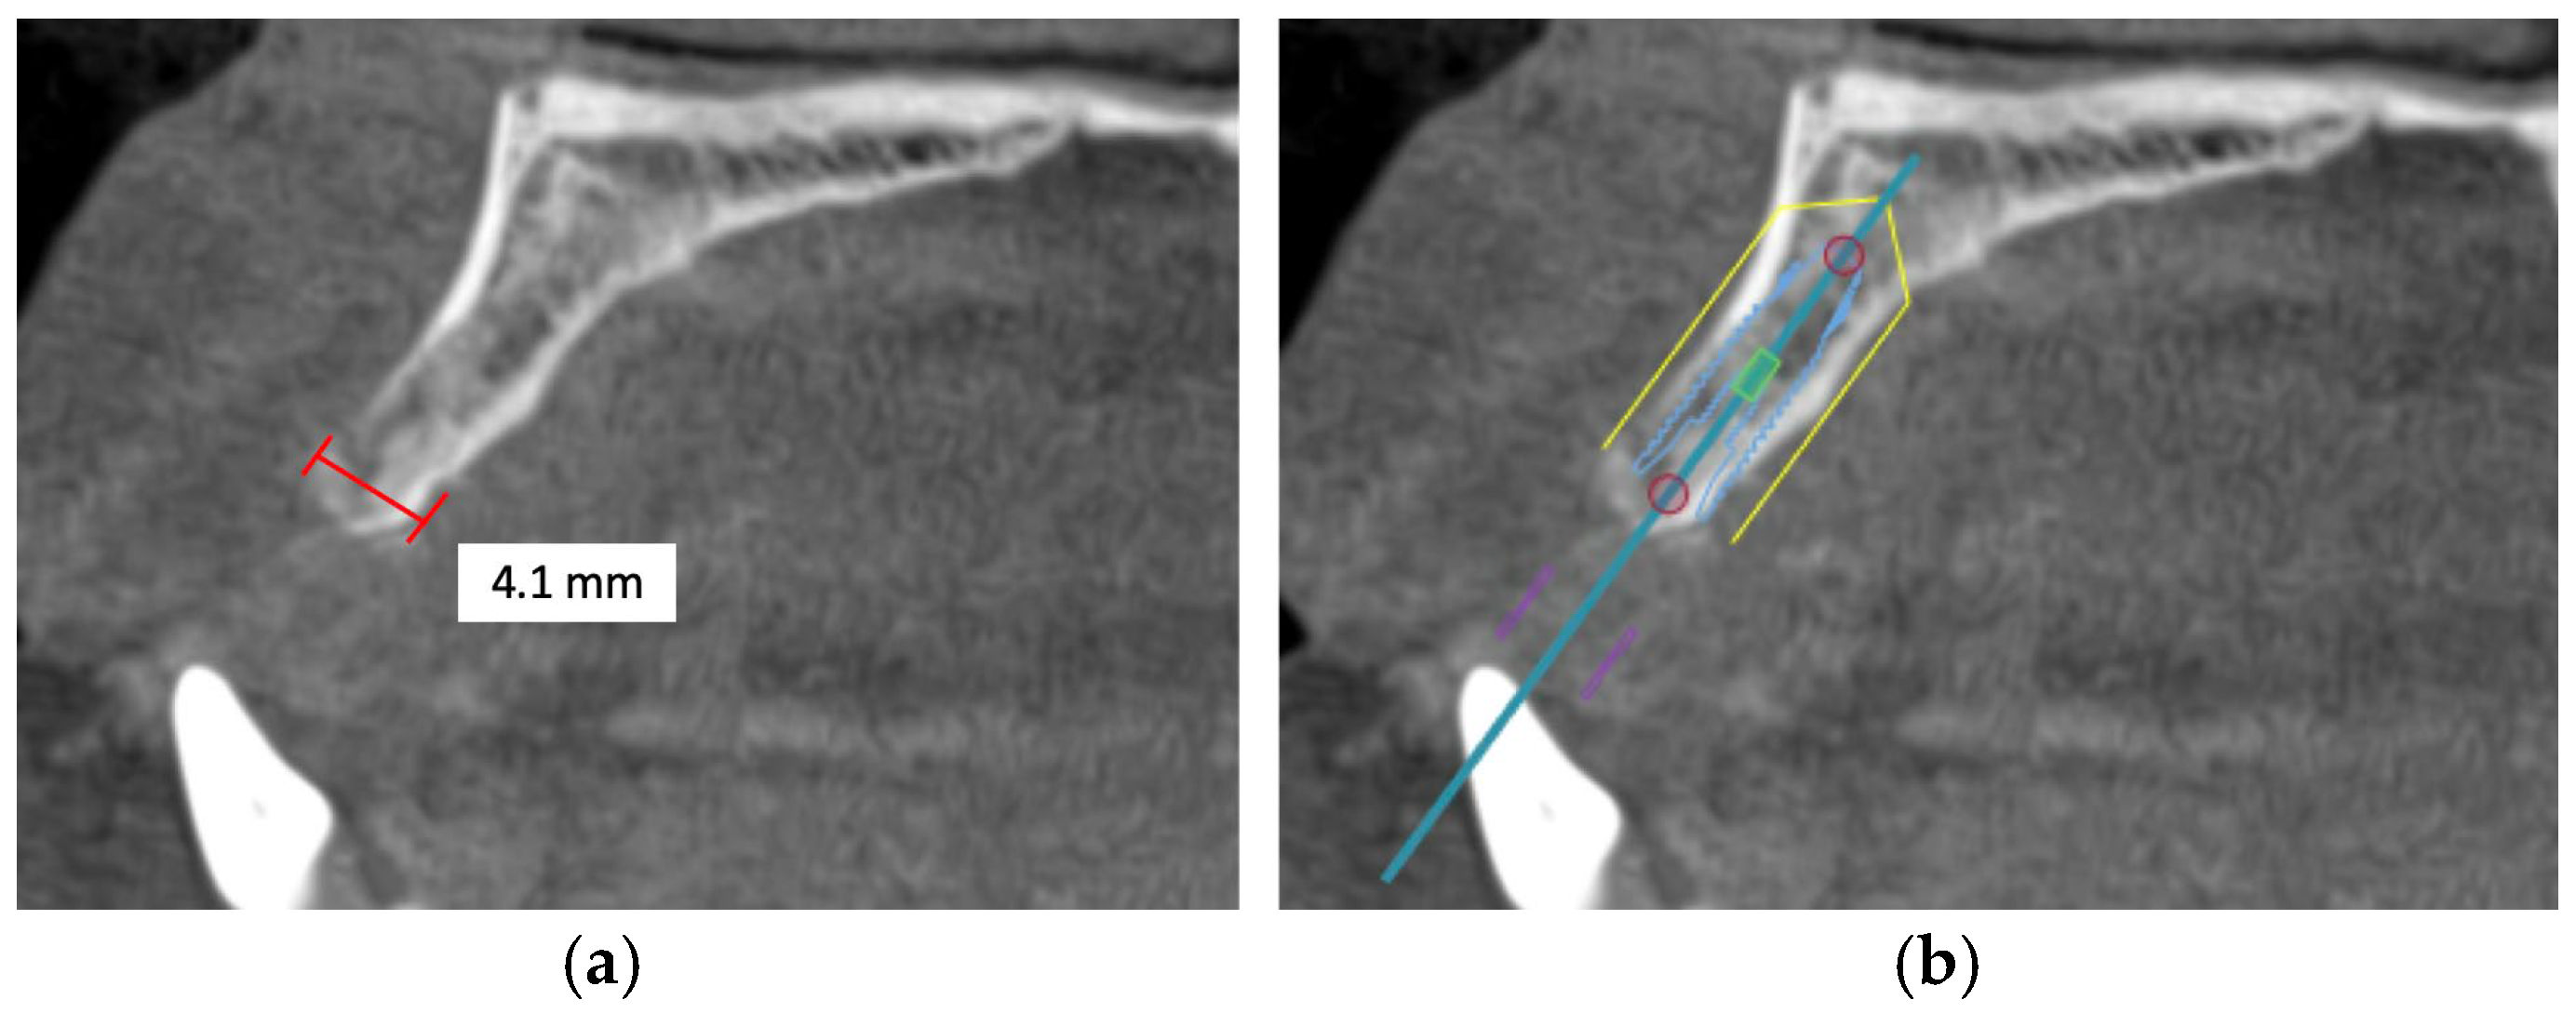

4.4. Available Bone Angulation